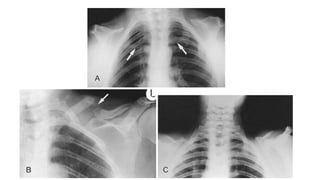

• Anomalous clavicular development

• The clavicle is formed from three separate ossification centers

(sternal, middle, and acromial). Because one or more of these centers

can be affected, there is considerable variation in the clavicular

involvement.

• In 10% of cases the clavicle is completely absent.

• The scapulae are often small, winged, or elevated.

• The shoulder girdle deformities allow great mobility of the shoulders.

• Chest is narrow and cone shaped.